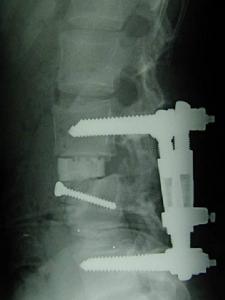

書名:脊柱外科實用技術

類別:醫學圖書